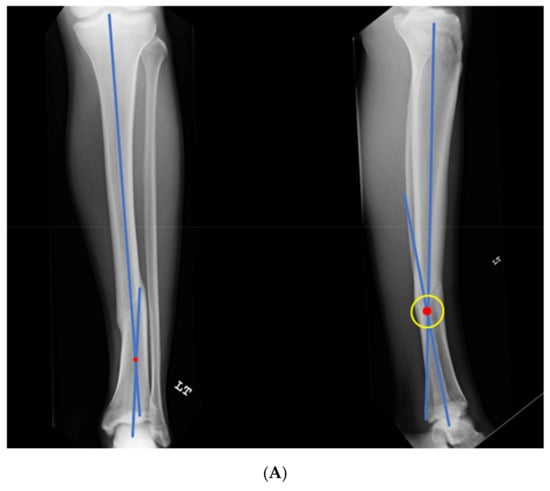

Figure 7.

(A) A young adult college baseball player sustained a closed tibia fracture with intact fibula, treated closed. The patient developed a recurvatum deformity with pain at the proximal and distal tibiofibular joints. (B) The patient demonstrated mechanical axis lateralization due to coronal plane translation with slight varus. The plane of deformity was calculated as 73 degrees off of the coronal plane. (C) The patient underwent focal dome osteotomy at the CORA (yellow circle) in the plane of maximum deformity. (D) Dual plate compression was used. Angulation and translation were simultaneously corrected. (E) Final follow-up 9 months: anteroposterior, lateral, and oblique films show the osteotomy healed. Tibiofibular joint pain resolved after osteotomy. Patient returned to college-level baseball.